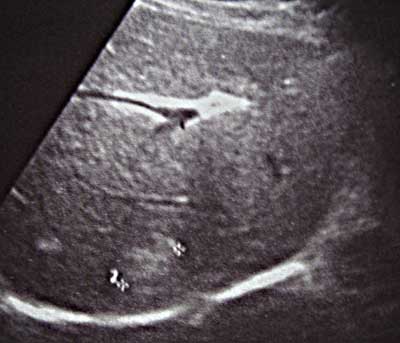

Женщина, 54года Профосмотр

Таких "штучек" у нее 7-8 по всей структуре печени(прошу прощения за качество снимков). Со слов, 2года назад было 3!

Заключение и дальнейшая тактика?